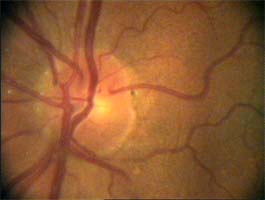

exkavace pravé oko

Na kterém oku je exkavace větší, na pravém nebo na levém? Podle pohledu na fotografie jistě na levém.

Co je příčinou toho, že při pohledu na snímky hodnotíme rozsah exkavace nesprávně? Je to skutečnost, že i růžová oblast neuroretinálního lemu může být již prohloubená, což vídáme zvláště na počátku rozvoje glaukomové neuropathie.

A jak se můžeme vyhnout záměně okrsku bledší barvy za skutečnou exkavaci? Tím, že budeme mít na paměti, že exkavace může být větší než nablednutí. Také zařazení zeleného filtru na pomůže snížit nežádoucí barevný kontrast.